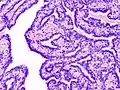

Histopathology of intraductal papilloma of the breast by excisional biopsy. Immunostaining for p63 protein.